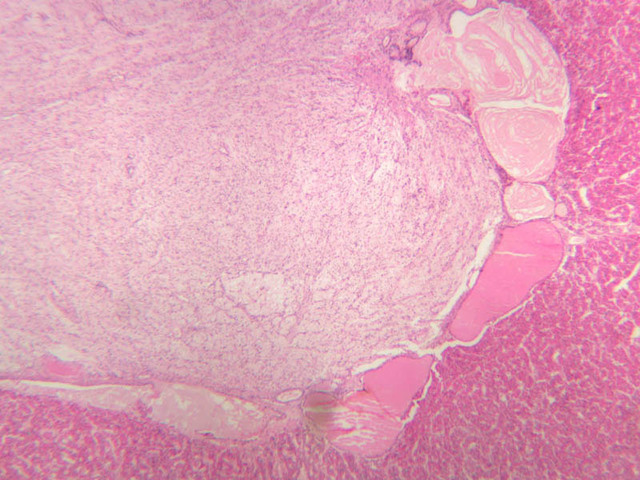

The adrenal gland (slide B-59, H&E [2.5x-labeled, 10x-labeled, 20x, 40x-labeled] [2.5x, 10x-labeled, 20x, 40x]; B-60, H&E [2.5x-labeled, 10x, 20x, 40x]; B-62, H&E [10x, 20x, 40x] [2.5x, 10x]) is a composite organ consisting of two functionally, structurally and embryologically different parts—an outer cortex and an inner medulla. Observe the gland at low power. Find the loosely organized tissue that comprises the medulla and the partially-separated columns of cells that make up the cortex. Scan the capsule and the tissue around it, looking for nerves and blood vessels. Study the pattern of cortical vasculature. In a pattern similar to that seen in the pars distalis of the pituitary, sinusoids run along the edges of columns or cords of cells. Owing to different arrangements of its constituent cells, the adrenal cortex has a layered appearance. From the capsule inward, these cortical layers are known as the zona glomerulosa, the zona fasciculata, and the zona reticularis.

The zona glomerulosa is located immediately beneath the capsule (B-60 adrenal gland, dog [10x, 20x] [20x, 40x]; B-59 [2.5x, 10x, 20x] [2.5x, 10x, 20x]). Its constituent cells are arranged in arcs or spheres, and, owing to their relatively small size, their nuclei appear to be close together. Cells of the zona glomerulosa secrete mineralocorticoids (e.g., aldosterone). The zona fasciculata consists of parallel columns or cords of cells that radiate toward the medulla and are separated by blood sinusoids (B-60 [2.5x, 10x, 20x, 40x]; B-62 [20x, 40x]). Owing to the extraction of lipids during histological processing, the cytoplasm of cells in the zona fasciculata appears highly vacuolated or "foamy". Cells of the zona fasciculata secrete glucocorticoids (e.g., hydrocortisone & cortisone) and some gonadocorticoids (weak androgens). The zona reticularis is the deepest cortical layer and lies adjacent to the medulla (B-60 [20x, 40x]; B-62 [20x, 40x]). It is characterized by irregular, interconnecting cords of cells which are separated by anastomosing capillary networks or sinusoids. Cells of the zona reticularis, which are smaller than those of zona fasciculata and do not contain as many lipid vacuoles, secrete gonadocorticoids and some glucocorticoids.

The medulla is composed of large epithelioid cells, arranged in small groups or cords which are separated by blood vessels. Usually, several large veins mark the center of the medulla. When fresh adrenal gland is incubated in solutions of chromium salts (as was the specimen on slide B-61), brownish precipitates form in the cells of the medulla-- hence, the name chromaffin cell (B-61, chromaffin [2.5x, 10x, 20x, 40x] [2.5x, 10x, 20x, 40x-labeled]). The more darkly stained chromaffin cells are known to contain norepinephrine, the less darkly stained cells, epinephrine. In essence, chromaffin cells are specialized postganglionic sympathetic neurons. How does the ultrastructure of these cells differ from that of the secretory cells of the adrenal cortex?